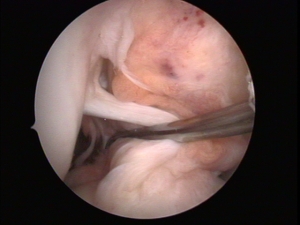

Cirugía Artroscópica